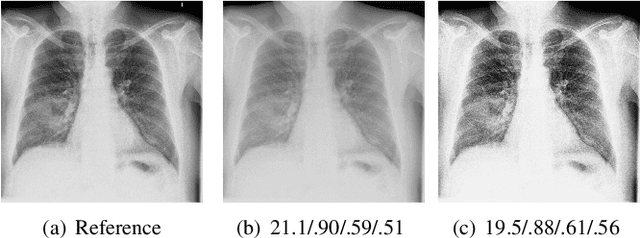

Abstract:When developing machine learning models, image quality assessment (IQA) measures are a crucial component for evaluation. However, commonly used IQA measures have been primarily developed and optimized for natural images. In many specialized settings, such as medical images, this poses an often-overlooked problem regarding suitability. In previous studies, the IQA measure HaarPSI showed promising behavior for natural and medical images. HaarPSI is based on Haar wavelet representations and the framework allows optimization of two parameters. So far, these parameters have been aligned for natural images. Here, we optimize these parameters for two annotated medical data sets, a photoacoustic and a chest X-Ray data set. We observe that they are more sensitive to the parameter choices than the employed natural images, and on the other hand both medical data sets lead to similar parameter values when optimized. We denote the optimized setting, which improves the performance for the medical images notably, by HaarPSI$_{MED}$. The results suggest that adapting common IQA measures within their frameworks for medical images can provide a valuable, generalizable addition to the employment of more specific task-based measures.

Abstract:Image quality assessment (IQA) is standard practice in the development stage of novel machine learning algorithms that operate on images. The most commonly used IQA measures have been developed and tested for natural images, but not in the medical setting. Reported inconsistencies arising in medical images are not surprising, as they have different properties than natural images. In this study, we test the applicability of common IQA measures for medical image data by comparing their assessment to manually rated chest X-ray (5 experts) and photoacoustic image data (1 expert). Moreover, we include supplementary studies on grayscale natural images and accelerated brain MRI data. The results of all experiments show a similar outcome in line with previous findings for medical imaging: PSNR and SSIM in the default setting are in the lower range of the result list and HaarPSI outperforms the other tested measures in the overall performance. Also among the top performers in our medical experiments are the full reference measures DISTS, FSIM, LPIPS and MS-SSIM. Generally, the results on natural images yield considerably higher correlations, suggesting that the additional employment of tailored IQA measures for medical imaging algorithms is needed.